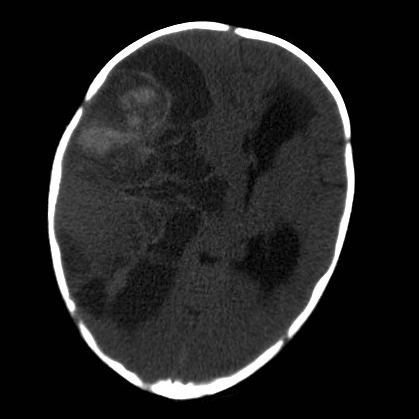

• U phôi và U nguyên bào thần kinh (Embryonal and Neuroblastic Tumors)

• U phôi sắp xếp kiểu hoa hồng (Embryonal tumor with multilayered rosettes - ETMR)

• U quái/u cơ vân dạng không điển hình (Atypical teratoid/rhabdoid tumor - AT/RT)

• U nguyên bào thần kinh di căn (Metastatic Neuroblastoma)

• U nguyên tủy bào (Medulloblastoma)